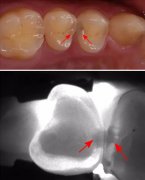

明明牙齿不肿不痛,为什么医生还是强调要定期做口腔检查? 因为,有些龋齿用肉眼并不能直接观察到,它们不存在于表面,而是隐藏在深处。初期一般没有明显症状,常常难以被注意到;..[详细]